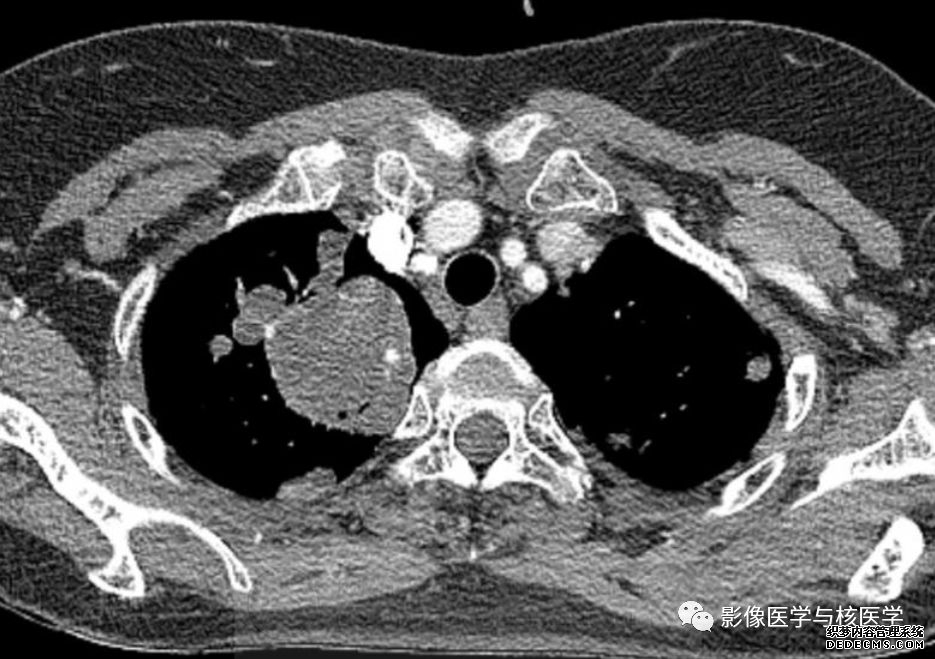

图2 胸部CT增强

图4 胸部CT增强

Figure 2-4. On chest CT after chest tube insertion in left hemithorax, there are multiple nodules and masses with/without cavity in both lungs.

图2-4.胸部CT显示左侧气胸置管后,两肺多发结节或肿块伴或不伴空洞。